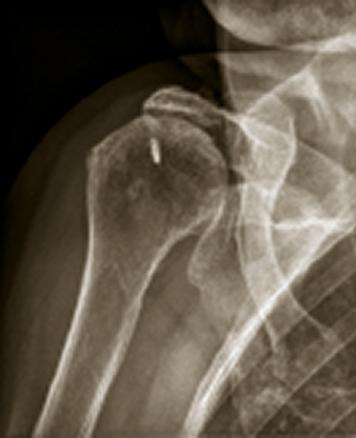

Omarthrose excentrée

Radiolographie d'une marthrose excentrée